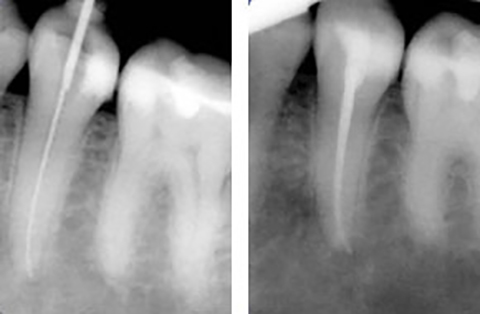

Ist der Zahnnerv durch Karies oder seltener, durch einen Unfall so geschädigt, dass er entfernt werden muss, wird eine Wurzelbehandlung notwendig. Dabei wird der Nerv entfert, der Zahn bzw. die Zahnwurzel gereinigt und desinfiziert und danach mit einem oder mehreren Kunstharzstiften gefüllt. Er bekommt eine Wurzelfüllung.

Wird diese Behandlung mit der notwendigen Sorgfalt durchgeführt, kann der Zahn danach, wie jeder gesunde Zahn, weiter seine Arbeit verrichten. Allerdings wird häufig nach einer Wurzelbehandlung, zum Schutz des Zahnes, eine adhäsive Kunststoffversorgung oder seltener eine Überkronung notwendig.